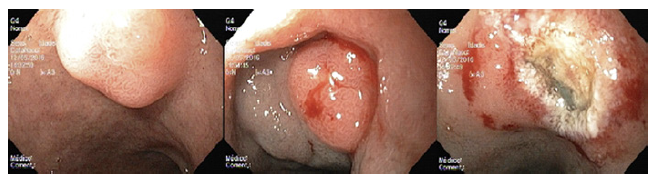

Standard EMR (EMRs) was defined as the conventional tech-nique of tumor resection with hot snare technique after submucosal injection with normal saline and diluted adrenaline (1:10,000 to 1:50,000 dilution) (Fig. 2). EMRc was performed with a transparent cap (Olympus, reusable oblique cap) at the tip of conventional upper GI endoscope and a crescent-type snare (EMR snare, Olympus). Hotsnare resection was done after submucosal injec-tion with normal saline and diluted adrenaline (1:10,000 to 1:50,000 dilution) and suction of the lesion into the cap. ESD was performed as previously described (Fig. 3). Briefly, small coagulation marks were made around the lesion and then submucosal injection was performed with saline, diluted epinephrine (1:50-100,000), and methylene blue. After elevation, 3-4 incisions were made with a needle knife (Olympus®) to get access to the submucosal layer, and an insulated-tip knife (mainly IT-KnifeTM; Olympus®) was used to perform circumferential dissection using the Endo Cut mode (Olympus electrosurgical unit, 80/60 W). Complete dissection was then performed in the Endo Cut or swift coagulation mode, with additional submucosal injection whenever necessary. The procedures were performed mainly under general anesthesia (with orotracheal intubation); deep sedation was restricted to a minority of procedures.